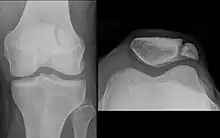

The patella can break in various ways depending on the way it is injured, and into two or more pieces.[1] Types include transverse, the most common, with one fracture line;[5] marginal; osteochondral; and the rare vertical type, or stellate, where a direct compression force gives rise to a comminuted pattern.[5][7] Patella fractures can be further classified as displaced, where the broken ends of bone do not line up correctly and separate by more than 2mm, or undisplaced and stable where pieces of bone remain in contact with each other.[1][7] If fragments of patella bone stick out from the skin it is known as an open patella fracture, and closed if the overlying skin is intact.[1]

Comminuted fracture of patella

Osteochondral fracture of patella